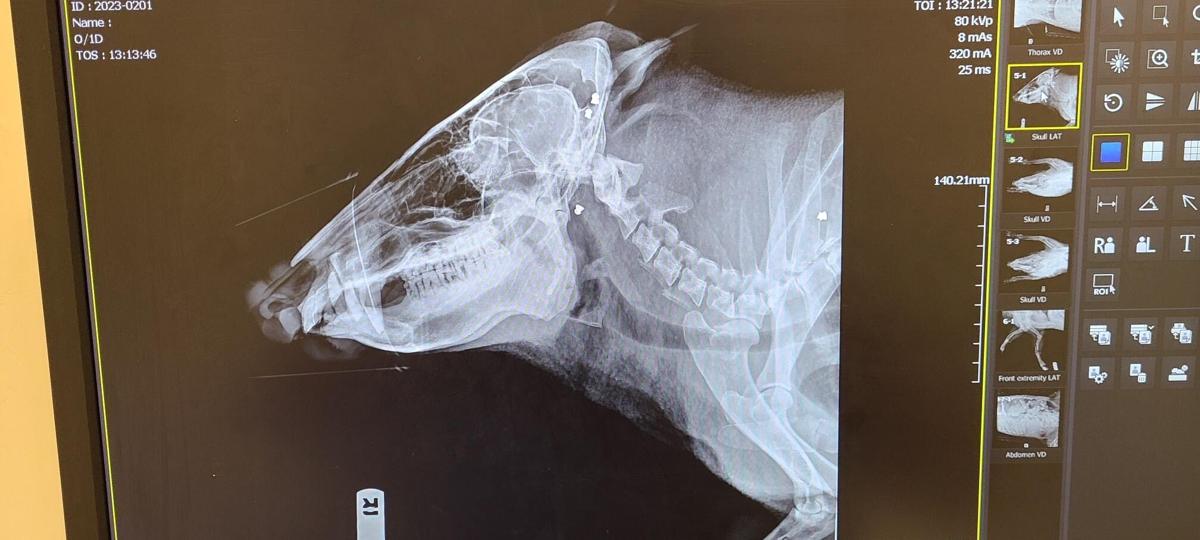

The javelina was shot 17 times, apparently with a pellet gun, officials said. The animal was found Feb. 28 by a passerby in the 38000 block of South Loma Serena Drive.

Another X-ray view of the wounds to the javelina.